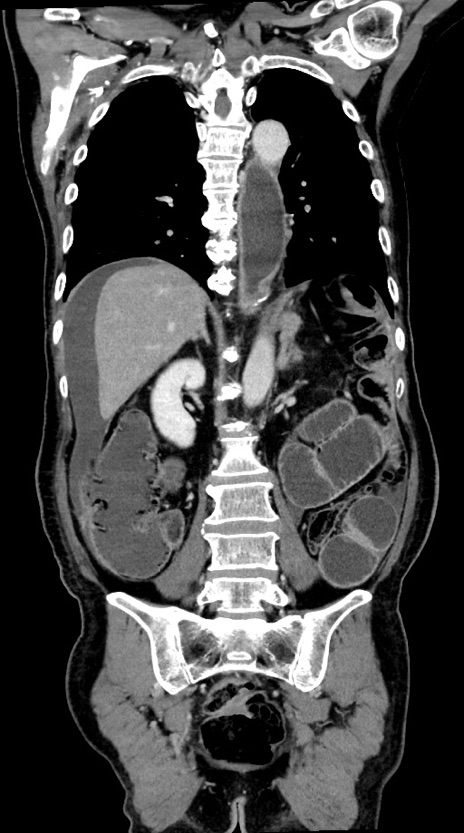

症例28(冠状断像)

【症例】60歳代男性

【主訴】嘔吐

【現病歴】胃癌にて胃全摘後。食思不振が悪化し、夜中に嘔吐することがある。

【既往歴】胃癌、胃全摘、脾摘、胆摘後

【データ】WBC 5900、CRP 10.56